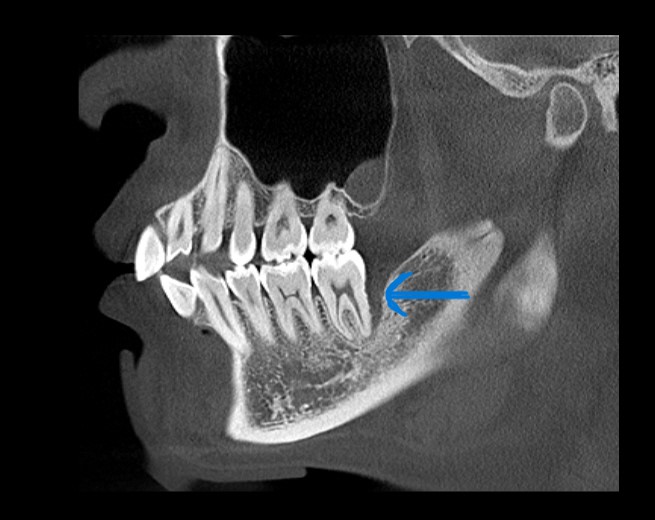

下の歯の奥側の骨が溶けてしまっています。

手術で歯ぐきを開き、徹底的に洗浄をし再生のための薬と人工骨を併用し、治療を行いました。

術後

レントゲン上で根っこの先端付近まで黒く抜けている部分が白くなっています。

骨が回復している様子が見られます。